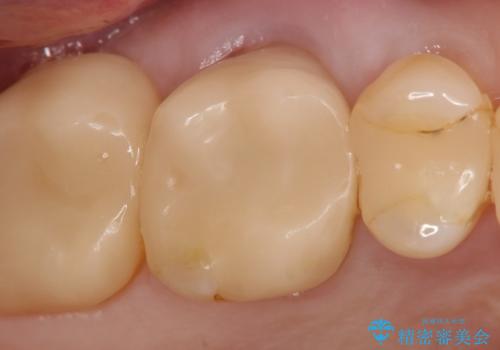

PGA(ゴールド)インレー しみる歯の治療